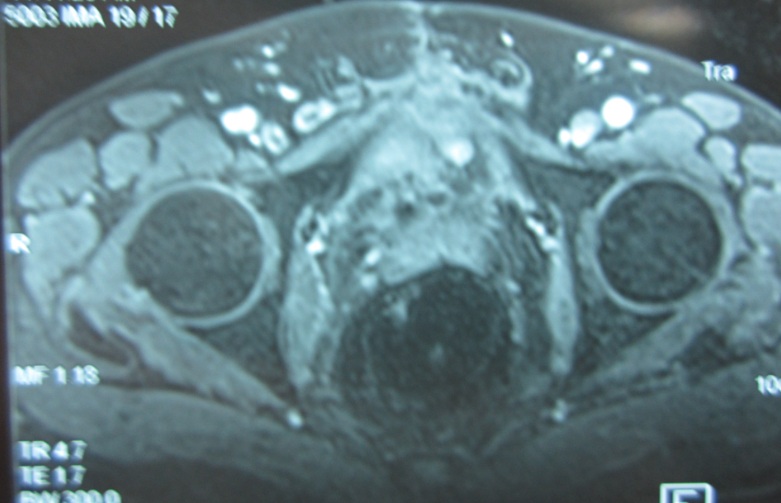

Kết quả sau liệu trình hóa - xạ trị: khối tổn thương tan hết trên hình ảnh cộng hưởng từ tiểu khung

Hình ảnh chụp MRI vùng tiểu khung: khối u tan hoàn toàn